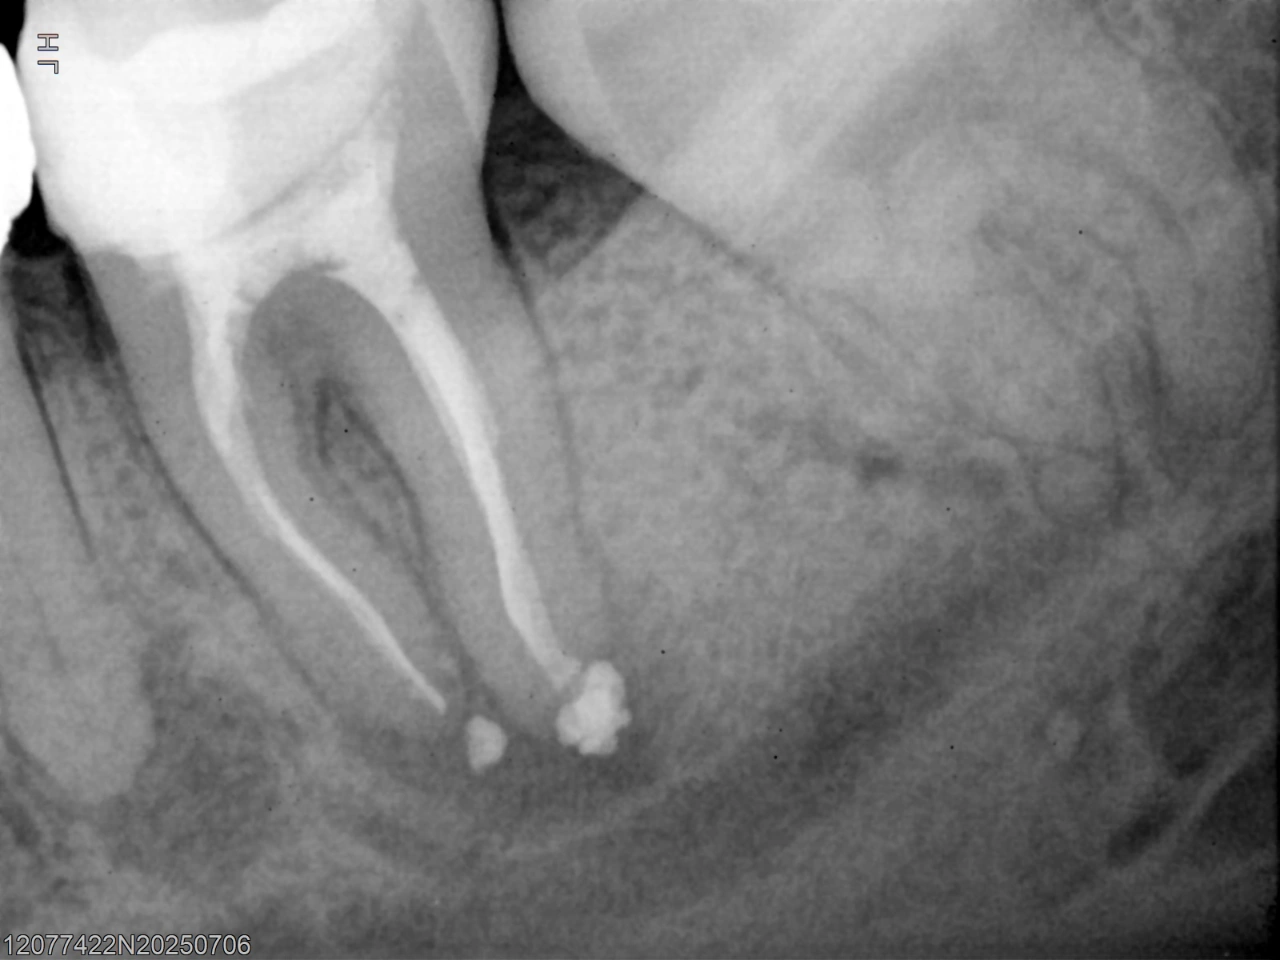

Pre-operative radiograph showing separated instrument

Initial Assessment: Radiographic evaluation revealed a previously treated lower second molar with a separated instrument within the canal.